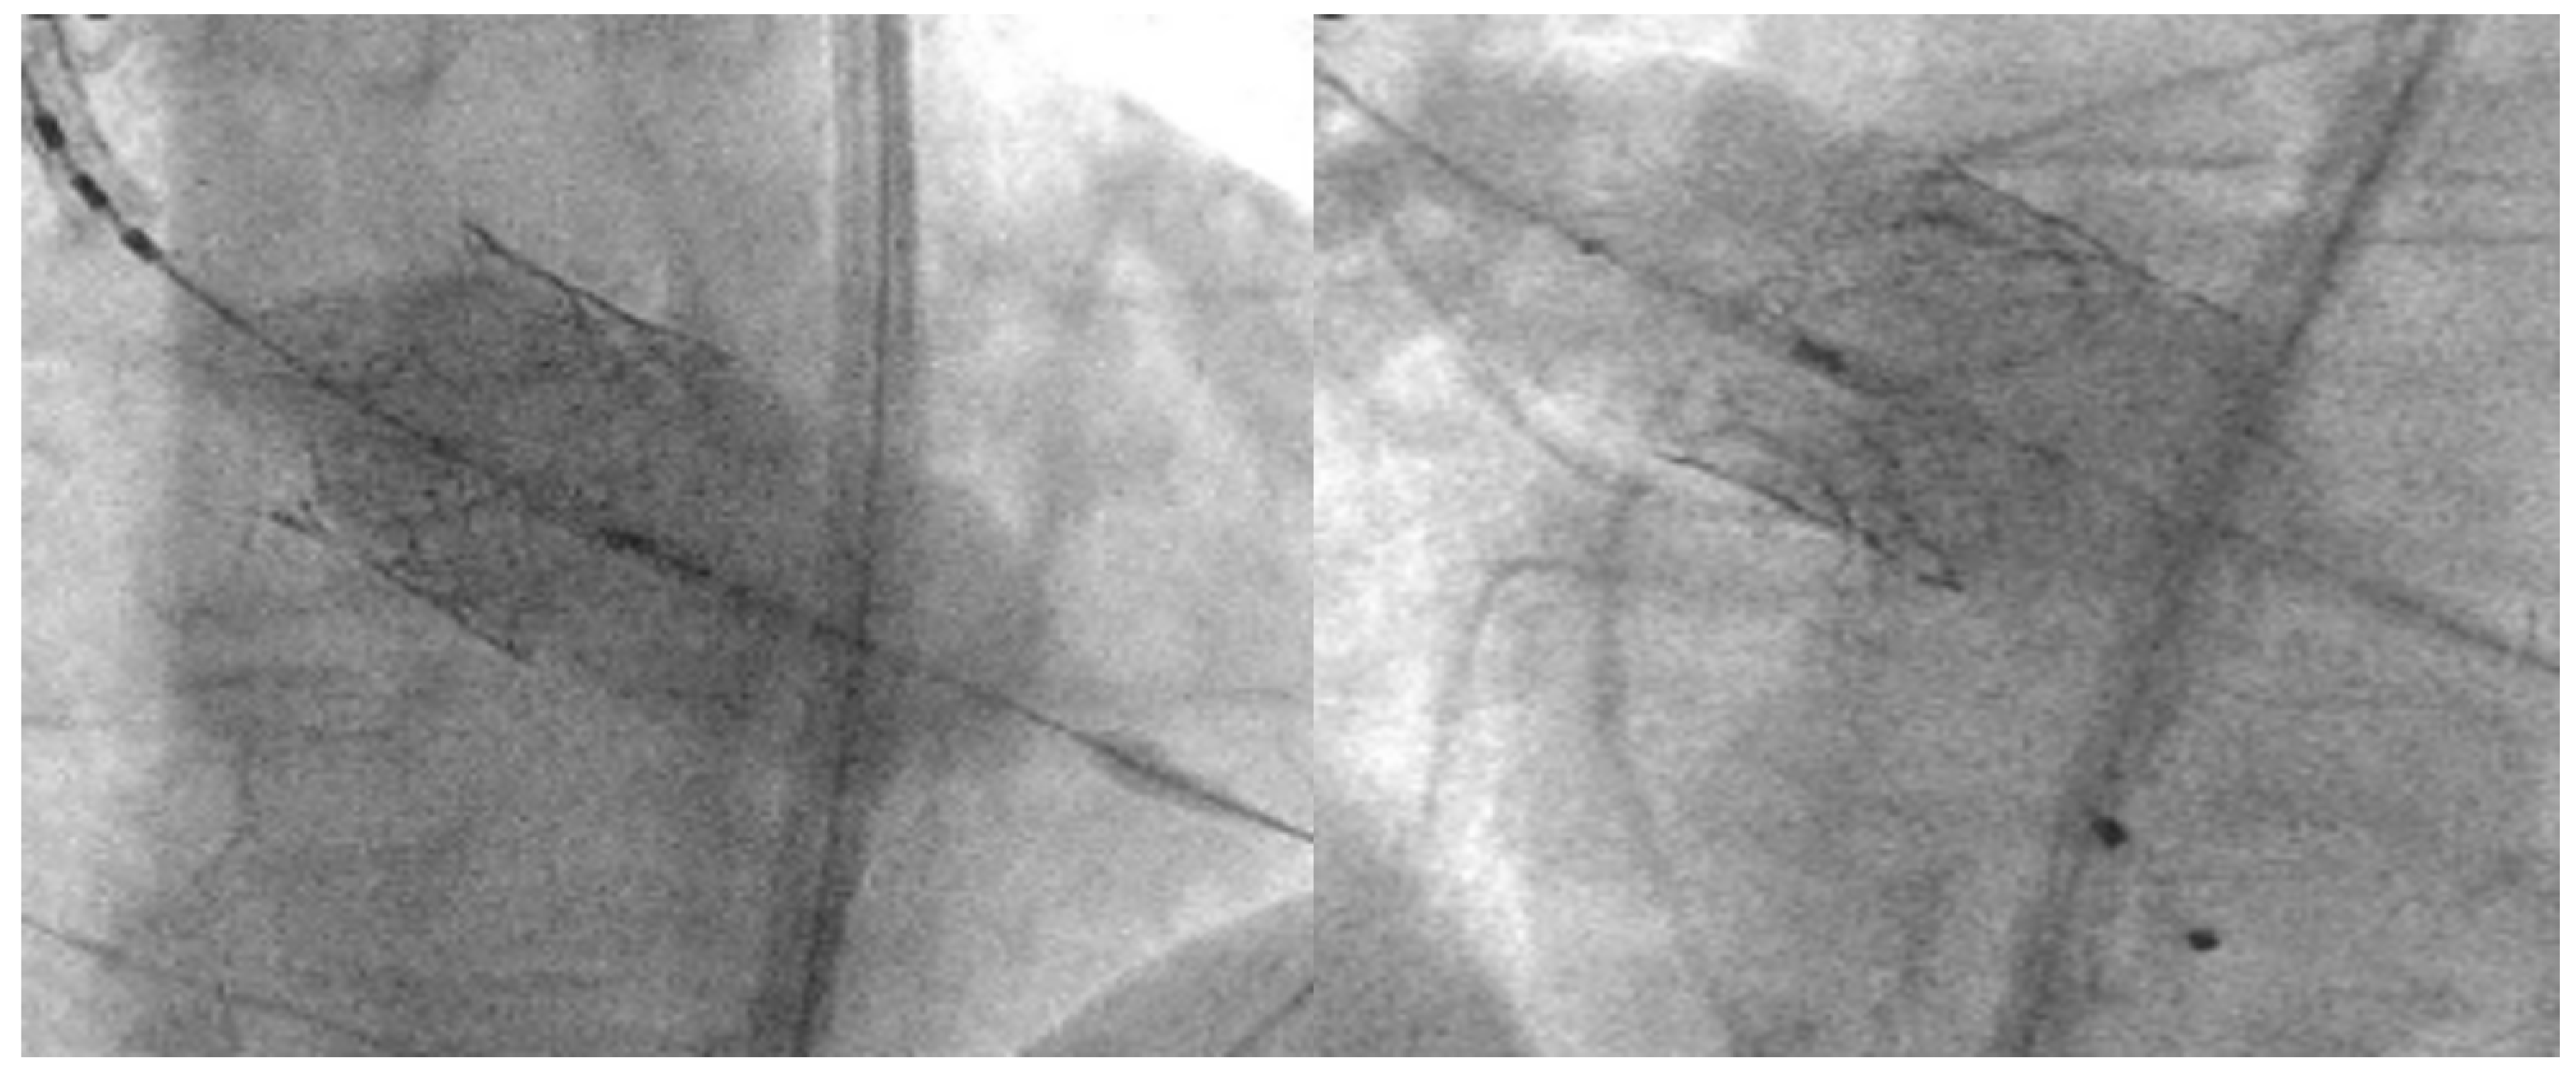

- Tchétché, D.; Siddiqui, S. Optimizing Fluoroscopic Projections for TAVR. JACC Cardiovasc. Interv. 2021, 14, 195–197. [Google Scholar] [CrossRef]

- Aljabbary, T.; Wijeysundera, H.; Radhakrishnan, S. Cusp Overlap Method For Self-Expanding Transcatheter Aortic Valve Replacement. Can. J. Cardiol. 2020, 36, S32–S33. [Google Scholar] [CrossRef]